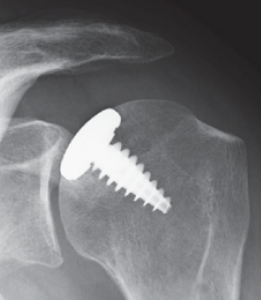

Bei jüngeren Patienten mit umschriebenen schweren Knorpeldefekten, die ohne Behandlung zur schweren Arthrose führen, werden so genannte Teil-Gelenkflächen (Hemi-CAP®) in die defekte Knorpelzone geschraubt (Abb. 45). Bei umschriebenen kleineren 4° Knorpelschäden besteht die Möglichkeit zur autologen Knorpelzelltransplantation. Dabei wird arthroskop. in einer ersten Operation Knorpel an der Schulter entnommen und für 6 Wochen im Labor angezüchtet. Der fertig gezüchtete Knochen wird dann in einem zweiten Eingriff in den Defekt eingepflanzt, der an dieser Stelle dann als vollwertiger Knorpel einwächst.